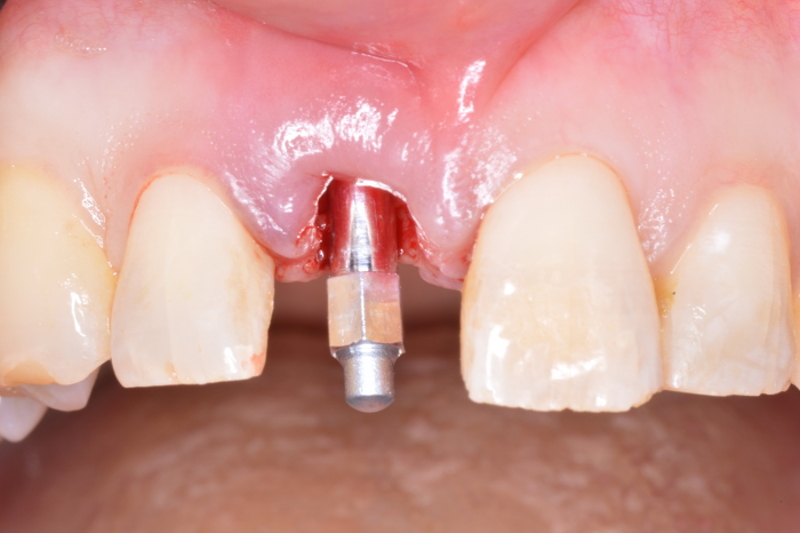

SmartPeg attached in order to record ISQ for an immediate implant replacing tooth #11 prior to immediate temporisation. (Image: Barry P. Levin)

Dr Levin, what is ITV and what is ISQ? ITV relates to the amount of energy or force—measured in N cm—required to rotate a screw-shaped implant into its designated position. It is a measurement of rotational implant stability. It is a one-time measurement, only determined at the time of implant placement. ISQ is a value obtained by resonance frequency analysis. It measures the stiffness of the implant material, of the implant–bone interface and of the surrounding bone (trabecular and cortical ratio). ISQ measures the axial stability of the implant; it is non-invasive and repeatable.

Why are these two important for immediate implant placement? Both ITV and ISQ measure the level of implant stability. Because they measure two distinctly different aspects of stability, they are both of importance and should be considered critical when temporising or permanently restoring implants.